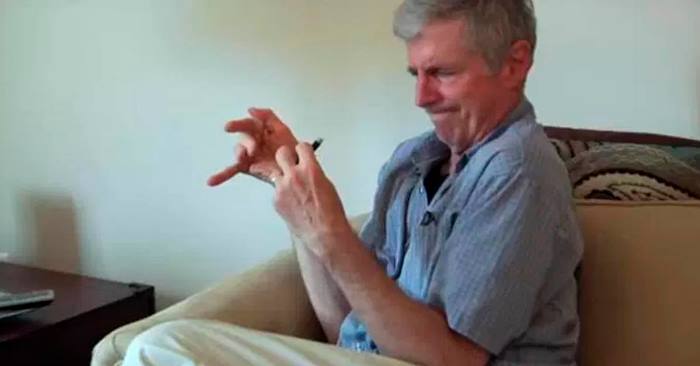

I dokumentaren «Ride with Larry», følger vi Larry Smith. Han jobbet tidligere som politimann, men han ble rammet av Parkinsons sykdom og måtte slutte.

Det er nå 20 år siden han ble rammet av sykdommen. Celler i hjernen som styrer bevegelser blir ødelagt, og han har slitt med skjelvinger i alle år. Frem til nå har han prøvd alle medisinene som er på markedet, uten at det har fungert. I videoklippet nedenfor får han derimot prøve medisinsk cannabis – og bare noen minutter etter han tar noen dråper i munnen, blir han en helt annen!

Når man ser dette korte videoklippet er det vanskelig å ikke være enig i at cannabis bør være lov i enkelte medisinske tilfeller.